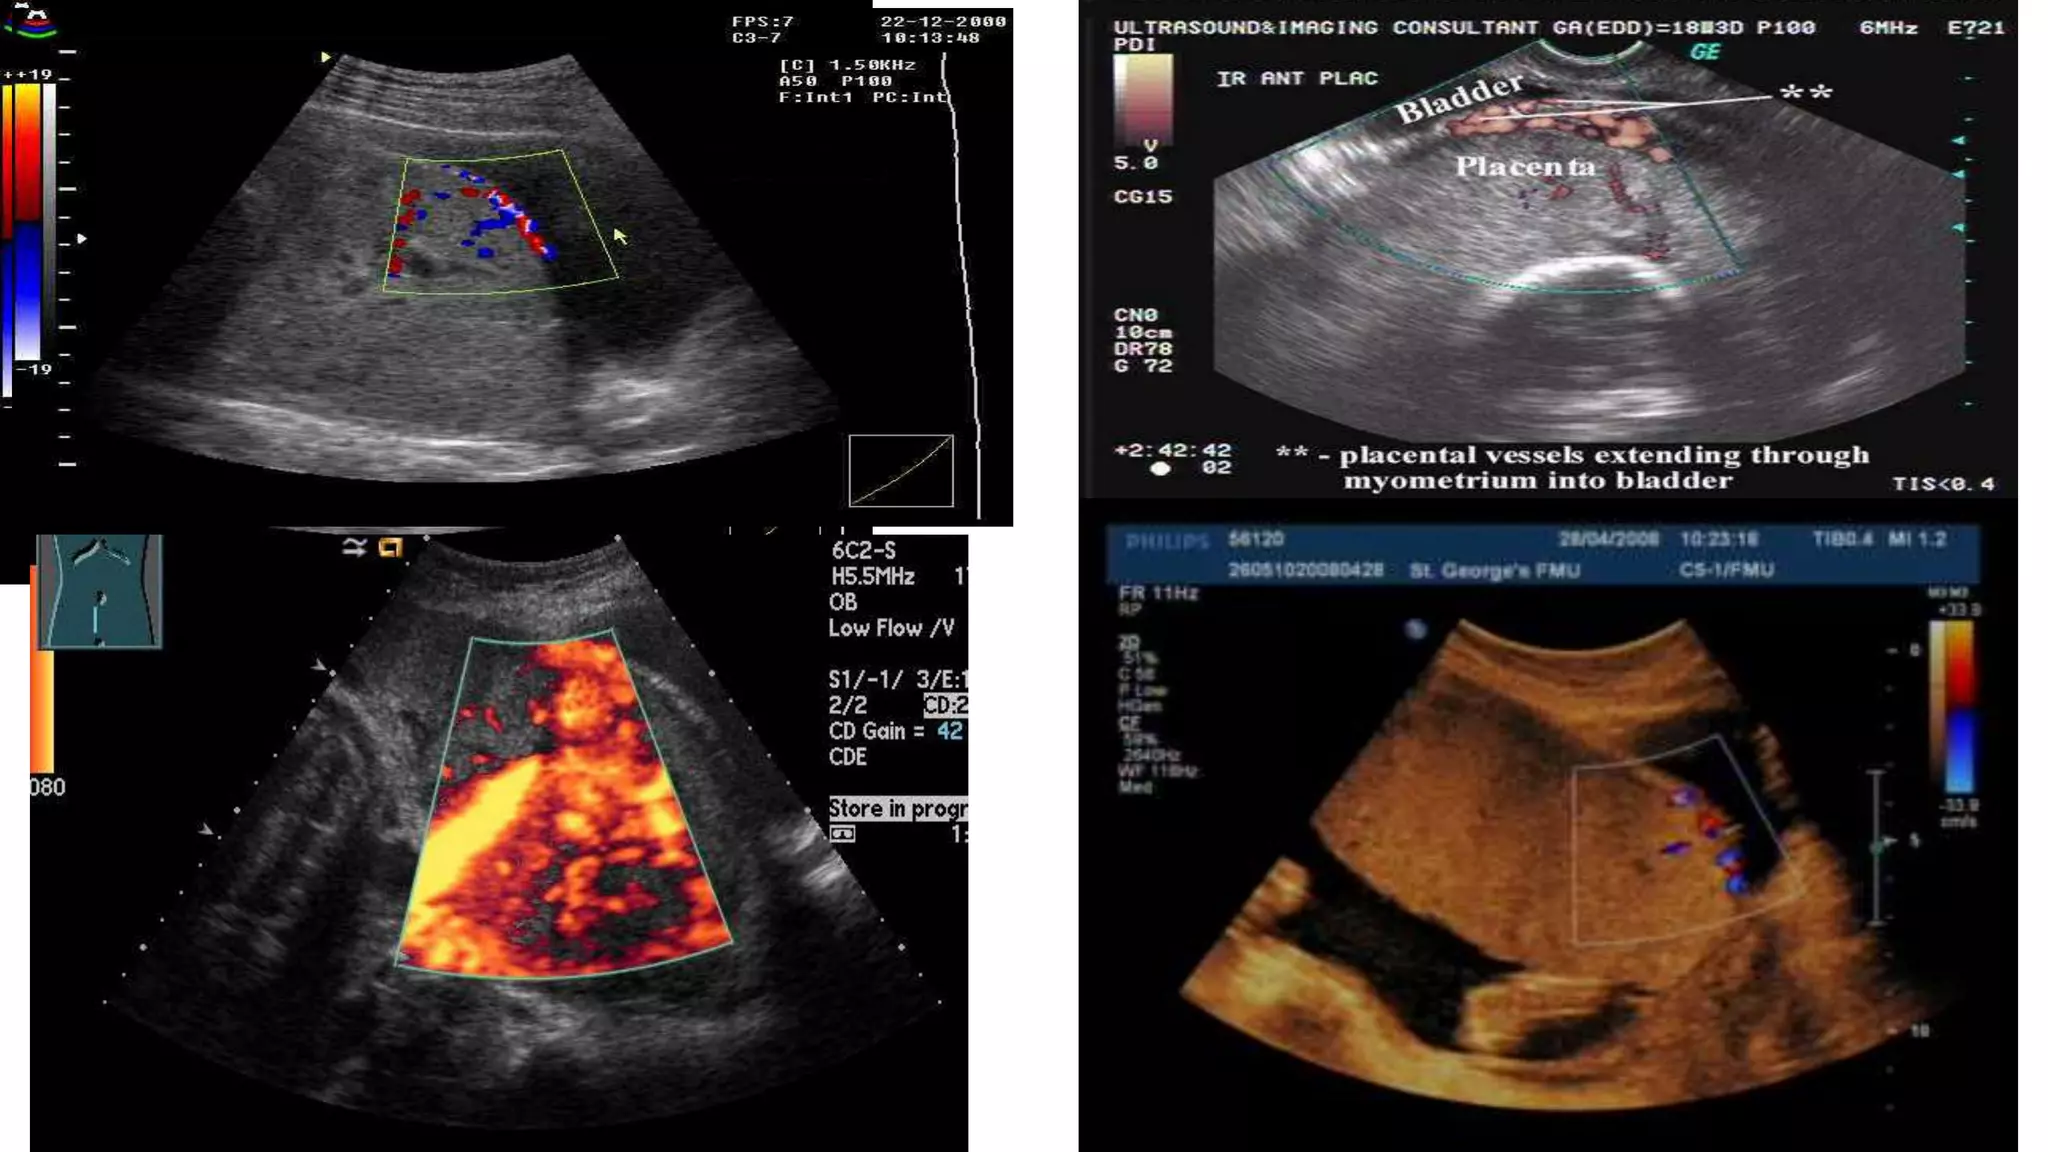

Color Doppler

• Used in conjunction with the other ultrasound findings.

• Abnormal vasculature on color Doppler ultrasound has the best

combination of sensitivity and specificity for prediction of invasive

placentation.

• Specific findings suggestive of placenta accreta include :

• Diffuse or focal intraparenchymal lacunar flow

• ● Vascular lakes with turbulent flow “chaotic”

• ● Hypervascularity of serosa-bladder interface

• ● Prominent sub-placental venous complex.

Three dimensional (3D) ultrasound

•Diagnostic criteria for PAS syndrome include:

•Irregular intraplacental vascularization with

tortuous confluent vessels crossing placental

width.

• Hypervascularity of uterine serosa–bladder wall

2nd and 3rd trimesters US findings suggestive of placenta

accreta

• Loss of placental homogeneity, which is replaced by multiple

intraplacental sonolucent spaces (venous lakes or placental lacunae)

adjacent to the involved myometrium. This is the most consistent

ultrasound finding.

• Loss or thinning of the normal hypoechoic area behind the placenta

(termed the ‘clear space’).

• Retroplacental myometrial thickness of <1 mm.

• Loss or disruption of the normally continuous white line representing

the bladder wall uterine serosa interface (termed the ‘bladder line’),

bulging of the placenta into the posterior wall of the bladder.